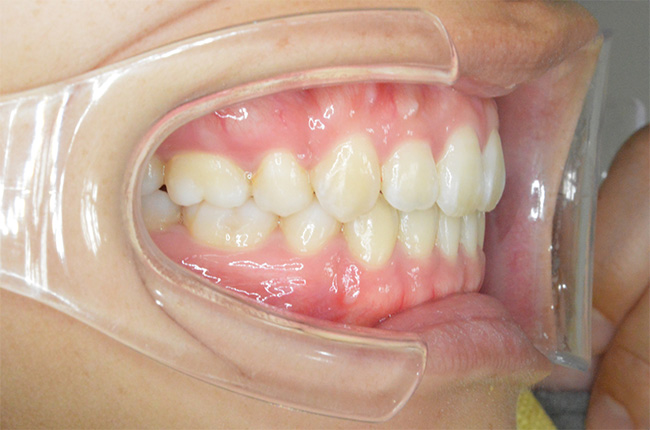

治療開始時